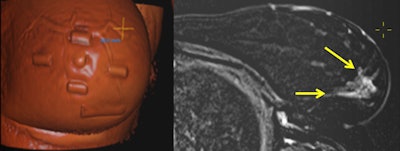

So far, few reports exist that deal with the positioning dilemma and transference of this information to the operating theater. So Joukainen, Masarwah, and colleagues sought to prospectively evaluate the feasibility of preoperative supine MRI using commercially available coils and breath-hold sequences to create accurate tools to transfer this information to breast surgeons using drawing charts and skin ink mark projections.

The researchers included 14 consecutive patients from Kuopio University Hospital, analyzing 15 breasts and 27 lesions (19 mass and eight nonmass). In addition to a diagnostic prone breast MRI scan (Philips Achieva 3.0T TX, Philips Healthcare), a supplementary supine 1.5-tesla MRI exam (Siemens Magnetom Aera, Siemens Healthineers) was performed with the patient in the surgical position, including skin markers.

Tumor locations were ink-marked on the skin according to findings obtained from supine MRI. The researchers measured changes in the tumors' largest diameter and locations between prone and supine MRI and compared them with histology. They also measured nipple-to-tumor and tumor-to-chest wall distances. Tumors and suspicious areas were surgically removed according to skin ink markings.